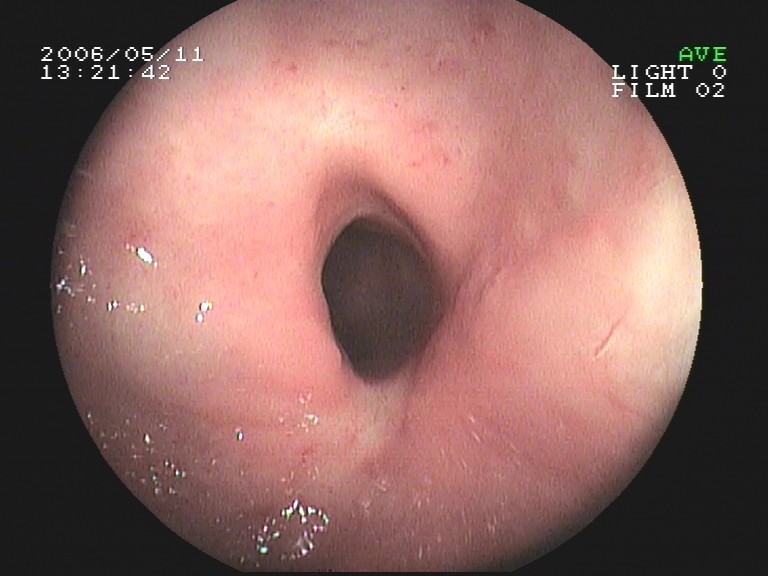

Coloskopie - Valvula Bauhini (Dünndarmklappe)